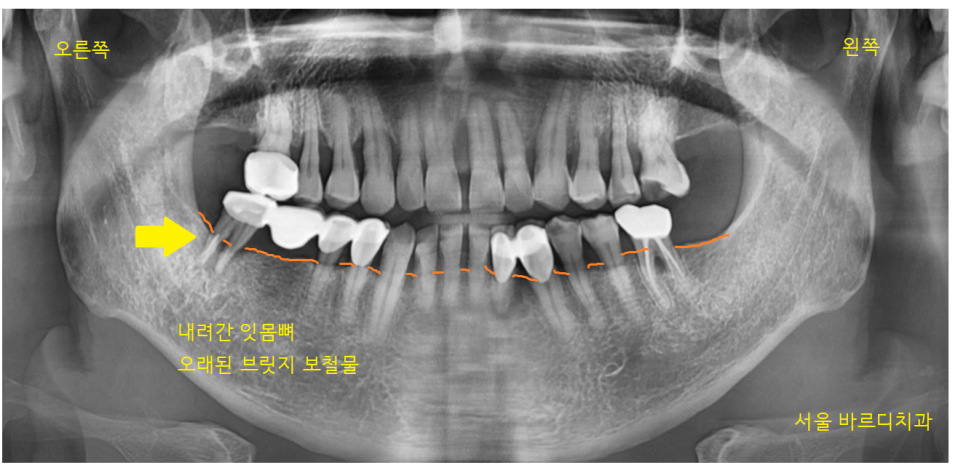

사진 속 화살표 치아를 주목해 주세요.

브릿지 치료가 되어있네요.

정상적인 잇몸뼈는 치아머리 부위까지

채워져 있어야 합니다.

잇몸뼈가 많이 내려가서

치아를 붙잡고 있는 게 없다 보니

흔들흔들했는데요.